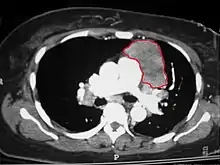

When a thymoma is suspected, a CT/CAT scan is generally performed to estimate the size and extent of the tumor, and the lesion is sampled with a CT-guided needle biopsy. Increased vascular enhancement on CT scans can be indicative of malignancy, as can be pleural deposits.[1] Limited biopsies are associated with a very small risk of pneumomediastinum or mediastinitis and an even-lower risk of damaging the heart or large blood vessels. Sometimes thymoma metastasize for instance to the abdomen.[5]

An encapsulated cystic thymoma.

A locally invasive circumscribed thymoma (mixed lymphocytic and epithelial, mixed polygonal and spindle).